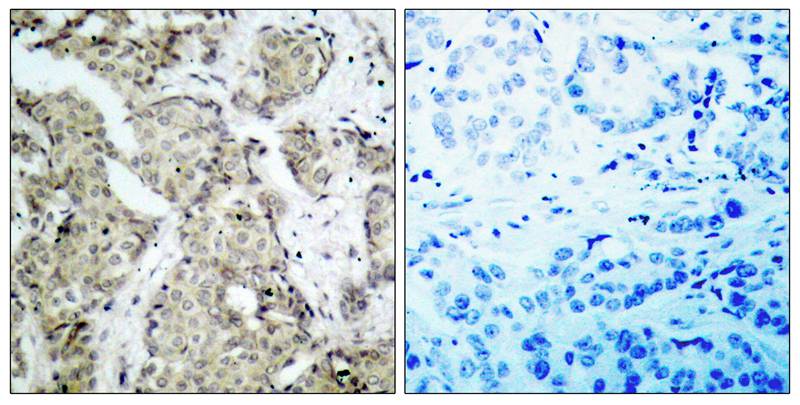

分类: 科研抗体货号: P40124别名: LIMK-2; kinase LIMK2;应用: WB,IHC,IF反应种属: Human,Mouse,Rat

分类: 科研抗体货号: P40122别名: ABL, JTK7, p150, c-ABL,应用: IHC,IF反应种属: Human,Mouse,Rat

分类: 科研抗体货号: P40121别名: PKB beta; Protein kinase B; RAC-PK-beta应用: WB,IHC反应种属: Human,Mouse,Rat

分类: 科研抗体货号: P40146别名: JAK-2; JAK2; Janus kinase 2; kinase Jak2;应用: WB,IHC反应种属: Human,Mouse,Rat

分类: 科研抗体货号: P40120别名: FADK 1; FAK1; PTK2应用: WB,IF反应种属: Human,Mouse,Rat

分类: 科研抗体货号: P40145别名: JTK10; THCYT3应用: IHC反应种属: Human,Mouse,Rat

分类: 科研抗体货号: P40119别名: Ataxia telangiectasia mutated homolog; Ataxia telangiectasia mutated; kinase ATM应用: WB,IHC反应种属: Human

分类: 科研抗体货号: P40143别名: tyrosine kinase 2; JTK1;应用: WB反应种属: Human,Mouse,Rat

分类: 科研抗体货号: P40118别名: ANDR; DHTR; AR应用: WB,IHC反应种属: Human

分类: 科研抗体货号: P40141别名: MAP kinase kinase 6; MAP2K6; MAPK/ERK kinase 6; MAPKK 6; MEK6应用: WB,IHC,IF反应种属: Human,Mouse,Rat